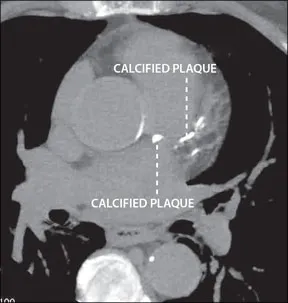

Use of computed tomography (CT) to assess the amount of calcified plaque in the coronary arteries is accepted as an alternative to catheterization in patients at low-to-intermediate risk for coronary artery disease (CAD) who present with chest pain. It is also becoming an increasingly popular method for routine CAD screening in asymptomatic patients as part of a comprehensive risk assessment. But a study in the July 13 Archives of Internal Medicine concluded that widespread use of this technology could dramatically increase the number of radiation-induced cancer cases in the U.S., with women especially at risk.